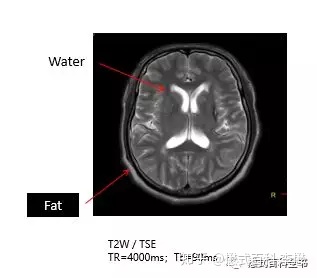

T2越长,在T2WI中,组织的信号强度越高,反映的是图像越白;

T2越短,在T2WI中,组织的信号强度越低,反映的是图像越黑。

脂肪组织是一种短T1,稍短T2的组织,这个是脂肪组织的特质参数。

如上图所示,是一个头颅的T2WI。同前面的分析一样。液体(脑脊液)是长T2的,在T2WI中,应该是高信号,是亮的,所以图中,脑脊液是白色的;而脂肪组织是稍短T2的,在T2WI中,是稍高信号,是白的,所以图中,头皮脂肪也是有点亮的。

这里要注意,脂肪比较特殊,理论上脂肪组织是稍短T2,在T2WI图像上,不应该这么亮。但是目前,磁共振T2WI所有序列均采用TSE进行扫描,因为是TSE序列,随着回波链延长,脂肪组织的信号会升高。

所以,无论是在T1WI图像,还是T2WI图像,脂肪组织都是亮的,反映在图像上都是白的。那么很多老师会说,在T2WI上,液体也是白的,脂肪也是白的,我们怎么判断呢?

液体(水),在T1WI上是黑的(暗的),在T2WI上是白的(亮的);

脂肪组织,在T1WI上是亮的,在T2WI上也是亮的;